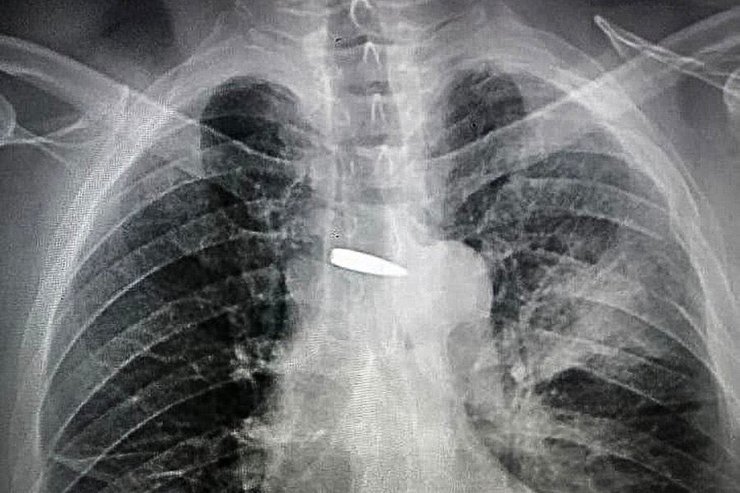

Віталій з Донеччини отримав поранення під час бою — куля пройшла крізь ліве плече, ліву легеню і буквально в міліметрі від серця, розбивши один із грудних хребців. Зараз він повернувся в стрій однієї з харківських бригад.

Віталій родом із Покровська Донецької області і зараз воює у лавах НГУ. Він не має позивного, а побратими просто називають його по-батькові Вікторович. Рентгенівські знімки серця нацгвардійця після поранення облетіли весь світ, оскільки куля влучила в груди чоловіка і пролетіла за міліметр від серця.

Куля пройшла крізь ліве плече і ліву легеню буквально в міліметрах від серця нацгвардійця

Як згадує Віталій, під час виконання бойового завдання він раптом відчув гострий пекучий біль в ділянці серця і побачив кров. Ворожа куля пройшла крізь його ліве плече і ліву легеню буквально в міліметрах від серця та роздробила поперечний відросток 5-го грудного хребця. Вікторовича доправили до Хмельницького, де місцеві лікарі визначили розміщення кулі до міліметра та завдяки сучасному обладнанню змогли її видалити. З операційної нацгвардієць навіть вийшов власними ногами.

"Про цей випадок майже всі ЗМІ розповідали, що там у Вікторовича всередині — вся країна бачила!" — жартують побратими чоловіка та показують фото кулі біля серця Віталія на рентгенівському знімку, який зберегли у своїх телефонах.